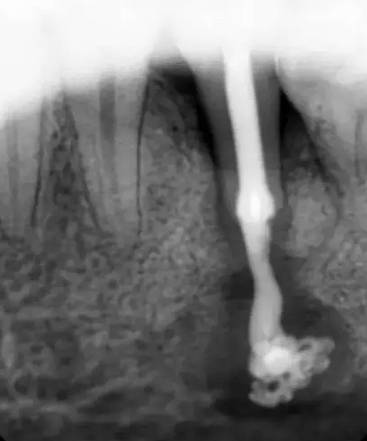

慢性根尖周肉芽肿慢性根尖周肉芽肿是根尖周组织受到轻微的感染刺激后产生的一团炎性肉芽组织。它是慢性根尖周炎的主要病变类型。一般无疼痛症状,有时有咀嚼乏力或不适。患牙多有深龋,牙髓多已坏死,牙齿变色,失去透明度,对冷、热诊及电诊均无反应,叩痛(—),但有时有异样感或叩痛,X线片示:有根尖周的骨质破坏区,即围绕根尖部的圆形或椭圆形边界清楚的透射区。

慢性根尖周脓肿慢性根尖周脓肿是慢性根尖周肉芽肿中央的细胞坏死、液化形成的脓肿;或急性根尖周脓肿处理不彻底,根尖部潴留的脓液被周围纤维结缔组织包绕而形成的。无窦型慢性根尖周脓肿症状与慢性根尖周肉芽肿大致相同,多无自觉症状。有窦型慢性根尖周脓肿患牙根尖部的颊、唇侧可见窦道口,窦道口也可能开口于远离患牙的位置,应仔细检查。X线片示:根尖部边界模糊的透射区,透射区周围骨质也较疏松。

慢性根尖周囊肿慢性根尖周囊肿是由慢性根尖周肉芽肿或慢性根尖周脓肿发展而来的。根尖囊肿生长缓慢,多无自觉症状。牙体可变黄色或深灰色,且无光泽,叩诊可有不适感,对冷、热诊及电诊均无反应;囊肿大小不等,发展较大时,可见根尖部相应软组织膨隆,表面不红,扪压富于弹性,有乒乓球感;囊肿过于肥大时,周围骨质被压迫吸收,可引起牙齿松动,或压迫邻牙使牙根吸收或邻牙移位。X线片示患牙根尖有圆形透射区,边界清楚,周围有白线围绕,此为诊断的重要依据。较小的根尖周囊肿与根尖周肉芽肿不好区分,大的根尖周囊肿应与颌骨囊肿及造釉细胞瘤相鉴别。